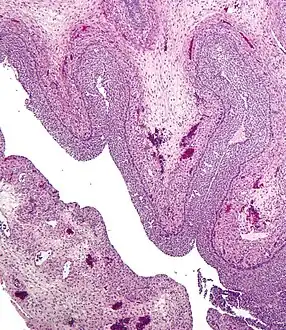

Human ovary with fully developed corpus luteum Luteinized follicular cyst. H&E stain.

Luteinized follicular cyst. H&E stain.

Pathology

- Corpus luteum cyst: hemorrhage into persistent corpus luteum. Commonly regresses spontaneously.